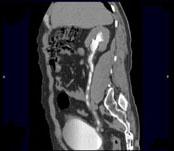

问题 男,47岁,腰痛、腰胀2个月余伴低热、乏力,如影像资料所示,下列哪项说法正确 ( )

选项 A、考虑为右输尿管占位病变 B、考虑为右输尿管结核 C、右侧输尿管多发性生理性狭窄 D、右侧肾盂轻度积水 E、右侧输尿管多发性狭窄,呈“串珠样”改变

答案 BDE